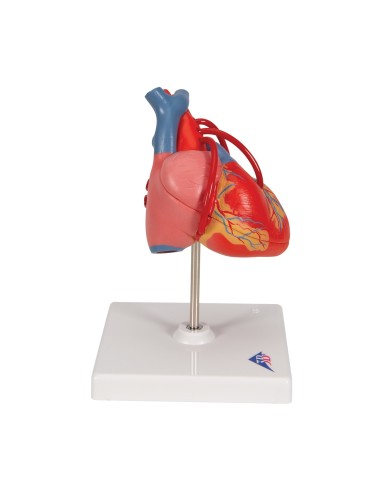

Per una migliore comprensione delle strutture anatomiche del cuore sono stati realizzati anche dei modelli anatomici di cuore ingrandito, si va dai piccoli ingrandimenti fino ai modelli di cuore per la formazione in aula, come il modello anatomico di cuore gigante prodotto da 3B Scientific: un modello di cuore ingrandito di ben otto volte.